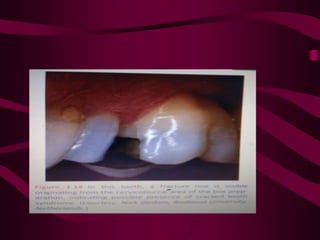

TRANSILLUMINATION

• Used to diagnose vertical fracture and cracks in

the crown.

• Uses a fibreoptic illuminating device horizontally

at gingival level.

• If a fracture exists, light will illuminate the side of

the crown that it contacts but the crown on the

opposite side remains dark.